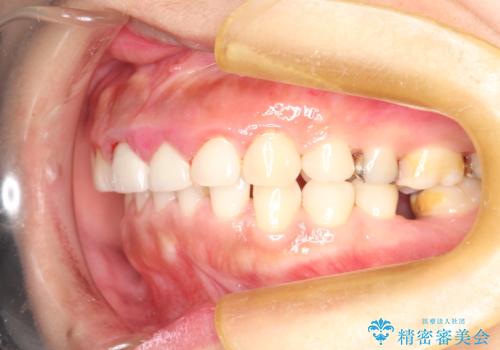

終了時

かなり久しぶりの歯科医院との事で、全体的に古くからの歯垢・歯石が多く付着していたため、自費クリーニング(PMTC)60分コース・歯周ポケット検査(保険適応)を行いました。

磨き残しが放置されると、そこで病原菌が繁殖し始めます。よって歯肉に炎症が生じ、歯周病の原因になることがあります。

定期的に、歯周病検査や専門的なクリーニングをすることで、早期発見につながります。